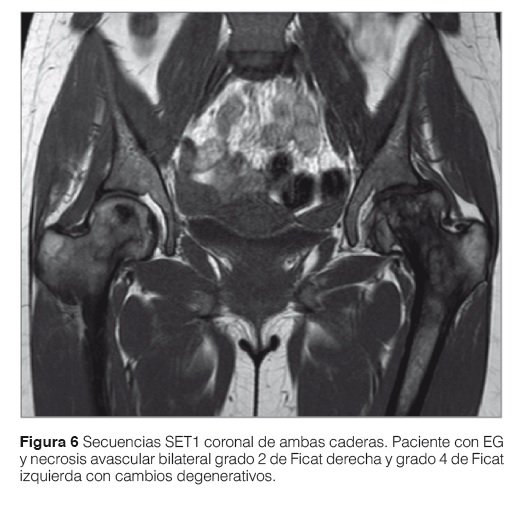

La combinación de secuencias SE T1 y Stir permite una exacta valoración de la médula ósea. El reemplazo de la médula ósea habitual por células de Gaucher (hipointenso) se ve reflejado claramente en las secuencias T1 y T2 sin saturación de grasa gracias a su calidad anatómica y alto contraste con la grasa hiperintensa normal de la MO grasa o amarilla. En secuencias SE T1 comprobamos el grado de infiltración, tipo de infiltración (homogéneo o heterogéneo) y el daño estructural óseo. En secuencias STIR se evalúa también la infiltración de la MO y pero principalmente y gracias a su gran sensibilidad al edema óseo (hiperintenso en Stir) se evalúa la presencia de lesiones agudas, destacándose las crisis óseas, los infartos, la necrosis avascular y las fracturas (Fig. 5).

Las lesiones óseas en la EG se clasifican en reversibles a la terapia de reemplazo enzimático (TRE) como la infiltración medular y la alteración en frasco de Erlenmeyer especialmente en la edad pediátrica y lesiones óseas irreversibles a la TRE: necrosis ósea avascular e infarto medular. La deformación en matraz de Erlenmeyer en un paciente en edad adulta debe ser considerada como lesión ósea irreversible (Fig. 6).